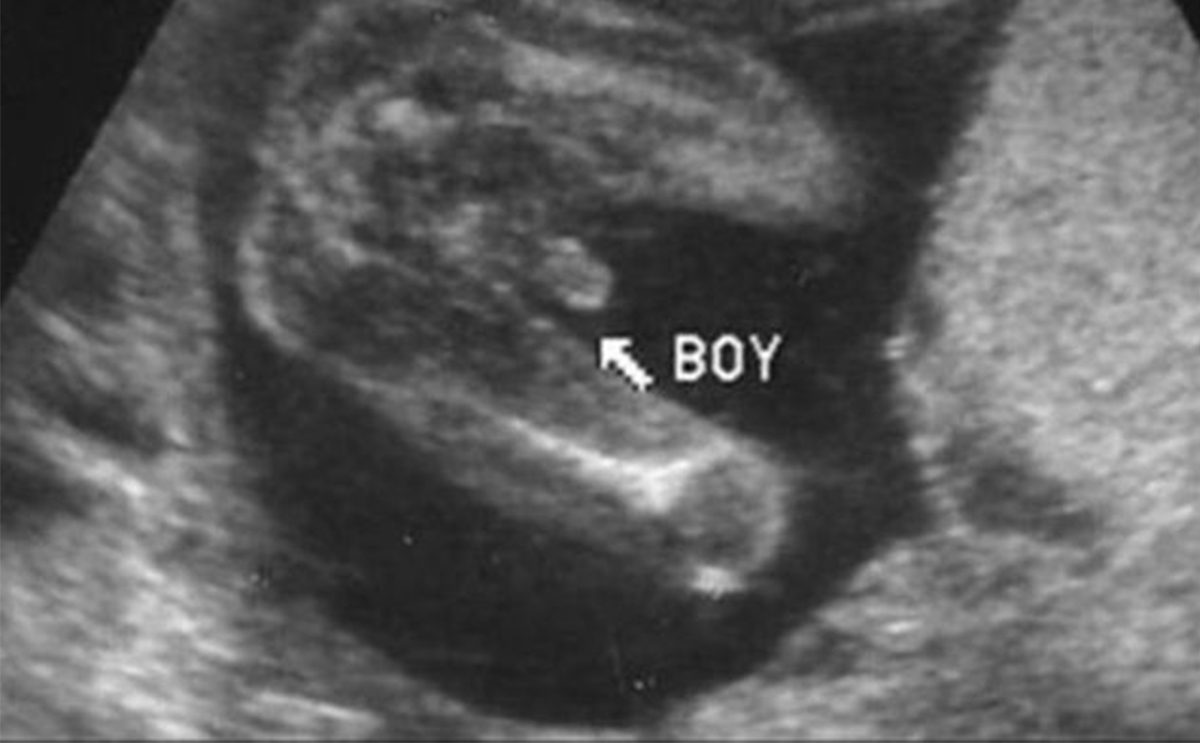

شكل الجنين الذكر بالسونار في الشهر الرابع

يعتبر تحديد الجنين الذكر أسهل من البنت ويمكن تحديد في مراحل مبكرة من الحمل وهذا لأن العضو التناسلي للذكر يكون واضحاً وبارزاً ومن السهل على الطبيب رؤيته بالسونار.